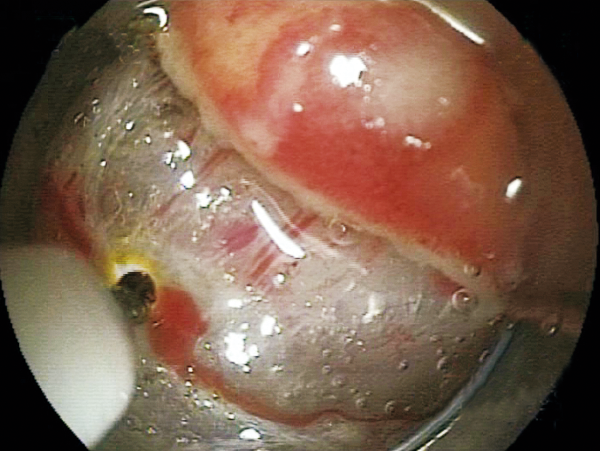

One knife covers 6 major functions for ESD, achieving high versatility

Able to incise the target tissue smoothly from side to side and up to down.

Injection of saline or submucosal injection agent*1 into the submucosal layer which is exposed after dissection can be performed.